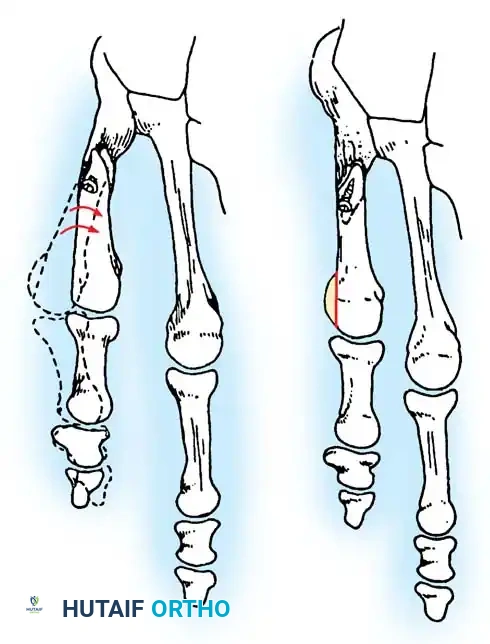

If conservative treatment fails and surgical intervention becomes necessary, the procedure must be tailored to the specific pathoanatomy (Fallat and Buckholz classification). The primary surgical choices are:

1. Partial Resection: Excision of the lateral third of the fifth metatarsal head (Lateral Condylectomy).

2. Osteotomy: Distal, midshaft, or diaphyseal osteotomy of the fifth metatarsal to correct angular deformity.

Causes of failure in lateral condylar resection include inadequate resection, MTP joint subluxation, and progressive forefoot splaying. Furthermore, if there is a painful callosity beneath the metatarsal head, the plantar aspect of the condyle must also be removed to prevent persistent plantar pain.

More metatarsal head can be removed than is intended if the medial edge of the articular cartilage is not adequately exposed. Approximately 35% to 40% of the metatarsal head is usually removed to excise the bony prominence. A thin osteotome or a small blade on a power saw is mandatory to prevent iatrogenic fracture or excessive bone loss.

- Osteotomy Cut: Score the proximal margin of the proposed osteotomy, and direct the cut in a dorsal distal–to–plantar proximal direction.